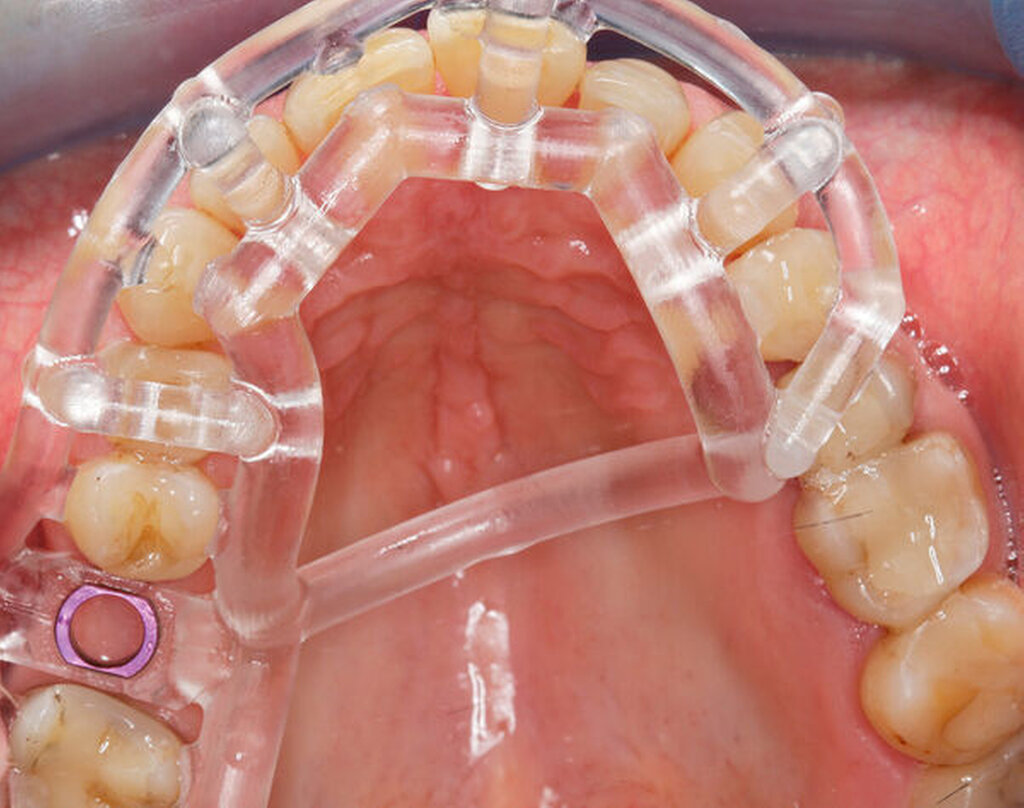

Im vorliegenden Patientenfall wurde die Implantation statisch navigiert mithilfe einer Bohrschablone und einer voll geführten Insertion durchgeführt (Abbildung 3). Dafür wurde der STL-Datensatz der Bohrschablone nach der Konstruktion in der IPS durch einen spezialisierten Mitarbeiter des Servicepartners DEDICAM (CAMLOG Vertriebs GmbH, Wimsheim) für die Bohrschablone zur Verfügung gestellt. Die Herstellung der Schablone erfolgte mithilfe eines 3-D-Druckers (Form 3, Formlabs GmbH, Berlin) im zahntechnischen Labor der Charité – Universitätsmedizin Berlin. Alternativ hierzu kann die Schablone auch vollständig fertig gestellt beim entsprechenden Anbieter bestellt werden.

Die genaue Gestaltung der Bohrschablone ist abhängig vom Bohrprotokoll und der Führungsmethode des jeweiligen Implantatherstellers. Beim vorliegenden Patientenfall und Implantatsystem fanden die Aufbereitung des Implantatbetts und die Implantatinsertion durch eine in die Schablone eingeklebte Metallhülse statt (Abbildungen 4 und 5). Sowohl die Bohrer als auch die Einbringpfosten erreichen dabei einen definierten Tiefenstopp (Abbildung 4).